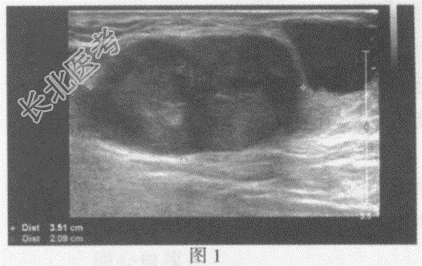

超声综合描述:左腹股沟区可见多个低回声(图1), 部分相互融合,最大3.5cm×2.1cm, 边界清晰,形态不规则, 内回声不均,CDFI: 内可见血流信号。左腹股沟区另可见多个不均质回声区(图2),最大2.1cm×1.8cm, 边界清晰,形态不规则, 内可见无回声区,CDFI: 不均质回声区内可见血流信号。